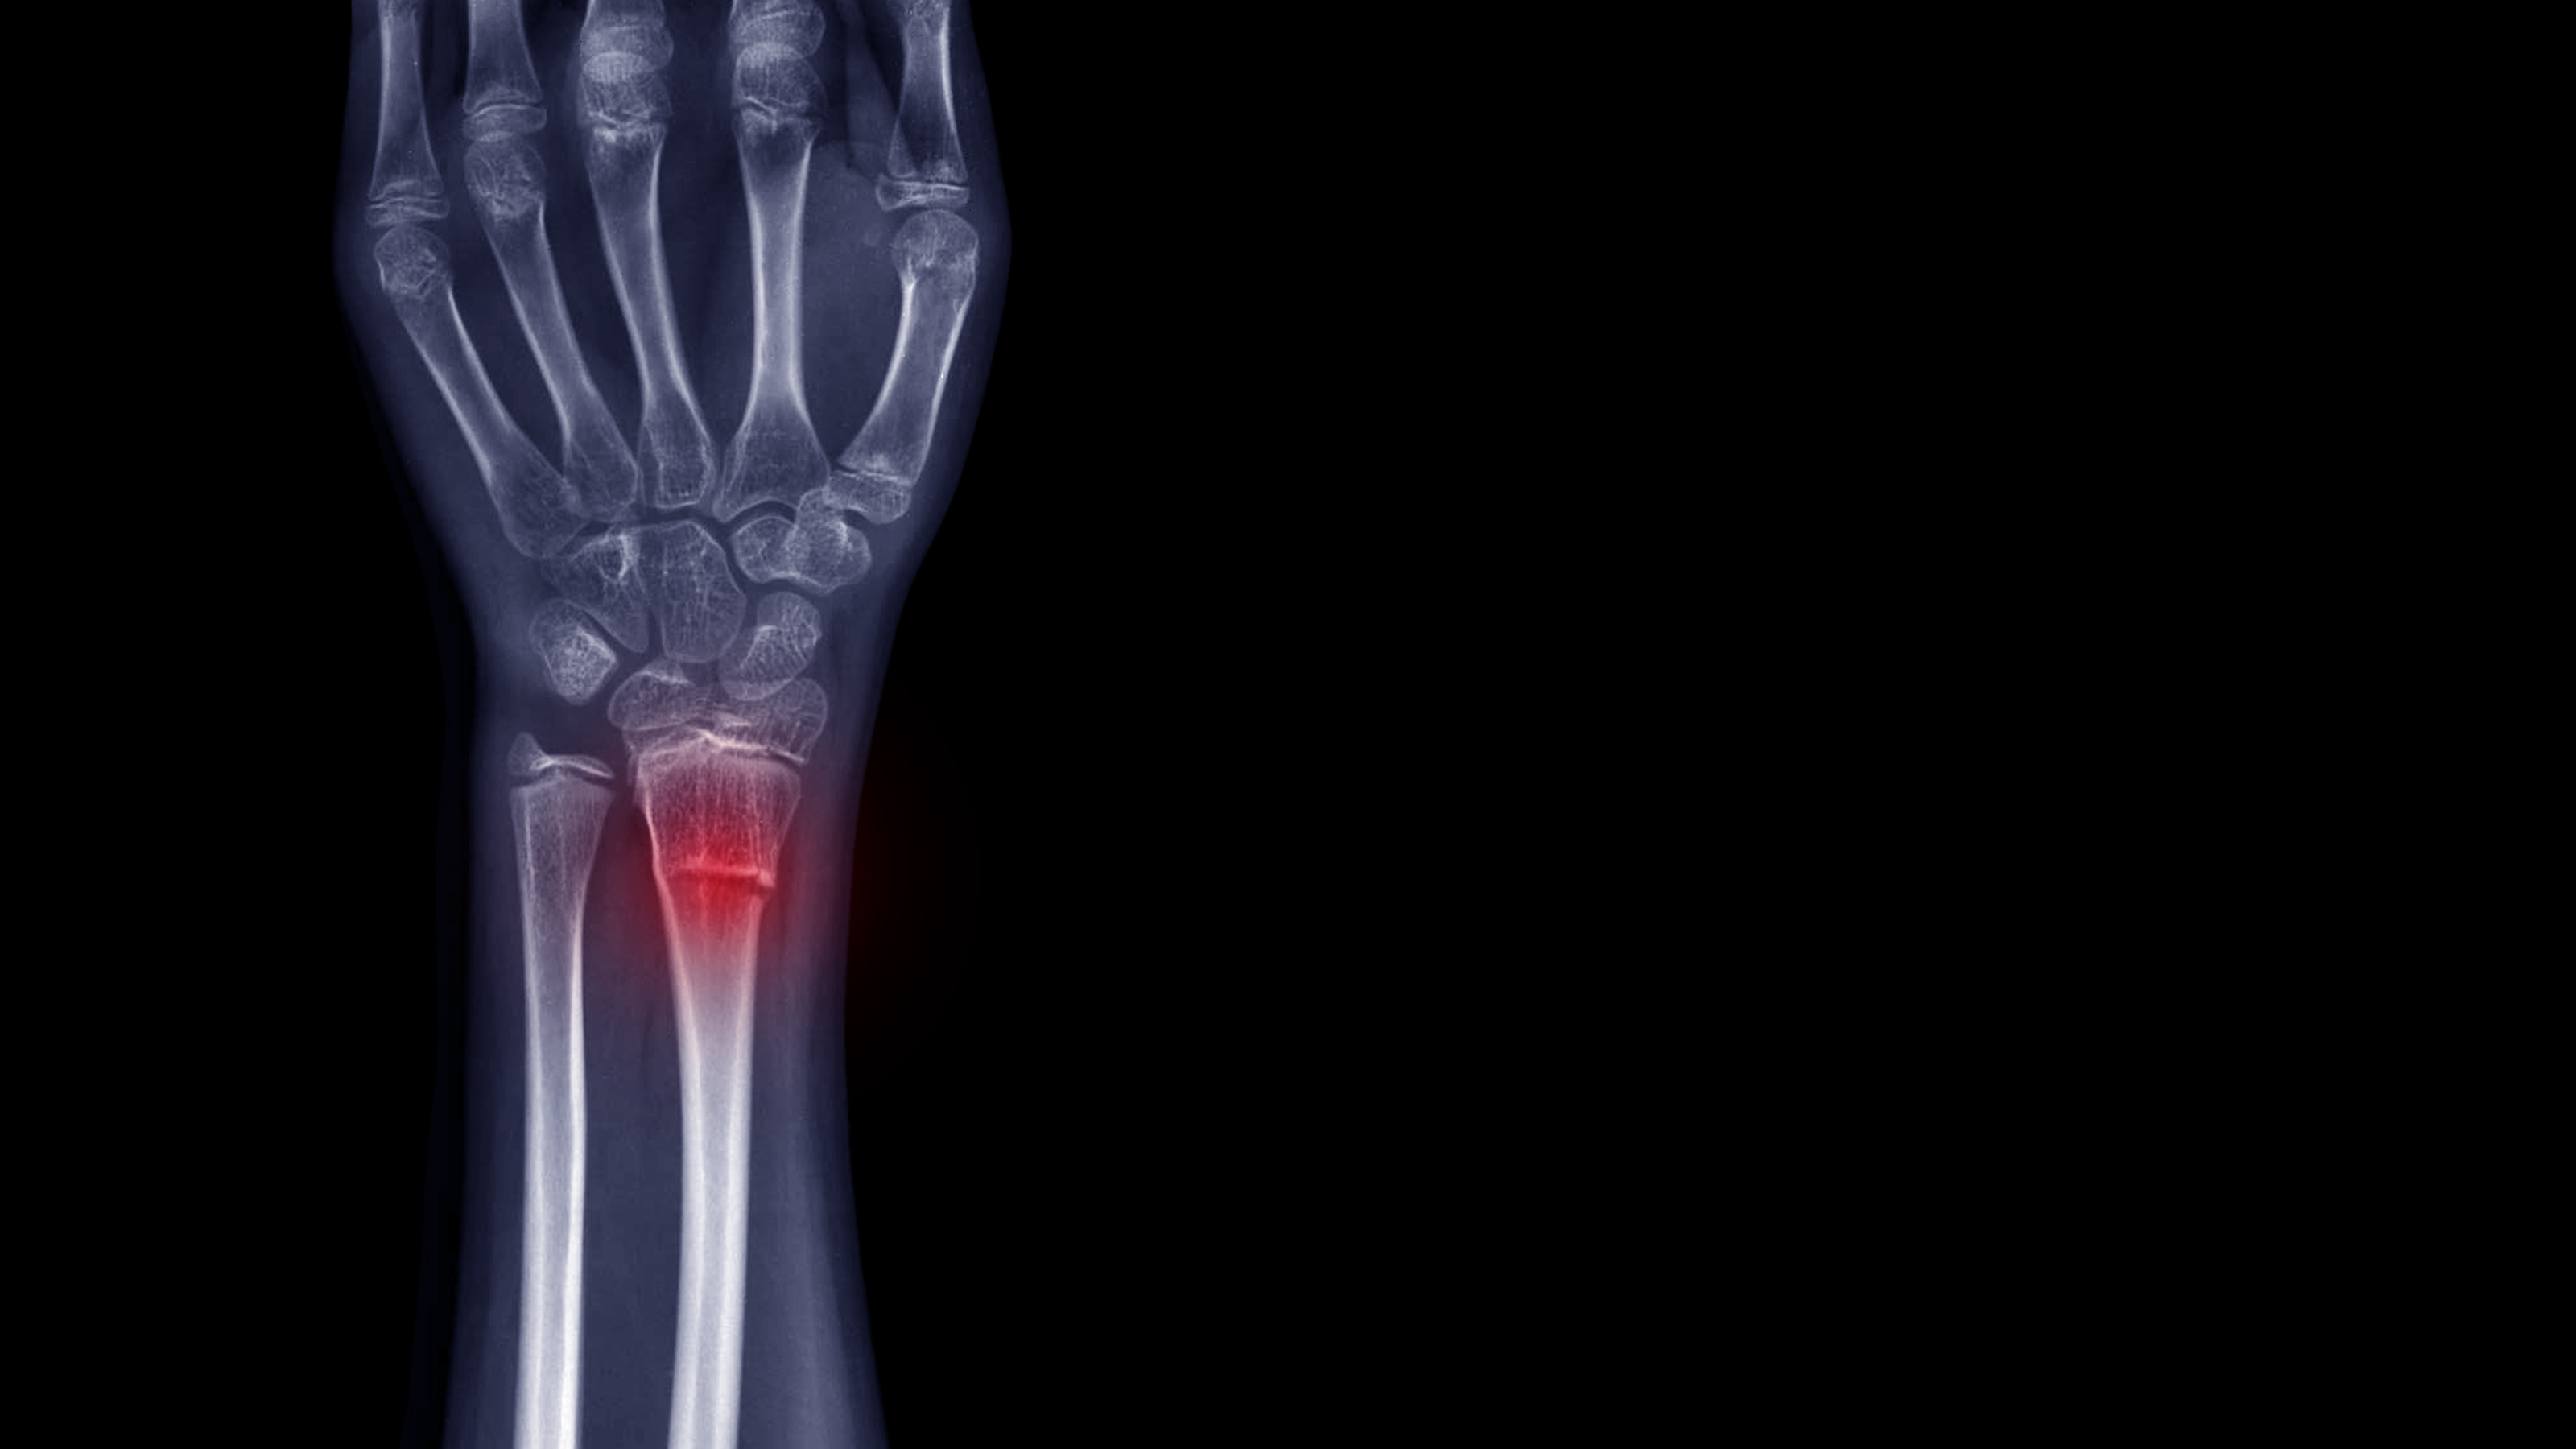

The forearm consists of 2 bones, radius and ulna.

Fractures of the forearm bones occur either near the wrist known as the distal fracture or in the middle part of the forearm or near the elbow in the upper portion of the bone, known as the proximal fracture.

Distal radial fractures are generally the most common types of bone fractures, the distal end of the radius bone being located near the wrist.